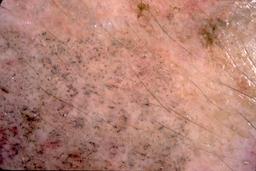

{

"age_approx": 20,

"anatom_site_general": "head/neck",

"concomitant_biopsy": true,

"dermoscopic_type": "contact non-polarized",

"diagnosis_1": "Benign",

"diagnosis_2": "Benign melanocytic proliferations",

"diagnosis_3": "Nevus",

"diagnosis_4": "Nevus, Atypical, Dysplastic, or Clark",

"diagnosis_5": "Nevus, Dysplastic",

"diagnosis_confirm_type": "histopathology",

"image_type": "dermoscopic",

"lesion_id": "IL_6012124",

"melanocytic": true,

"patient_id": "IP_6424174",

"sex": "female"

}